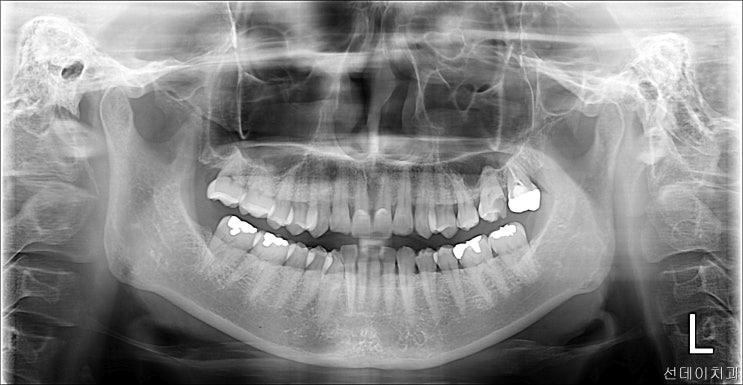

사랑니 뽑지 않아도 되는 관리 방법 알려드립니다!